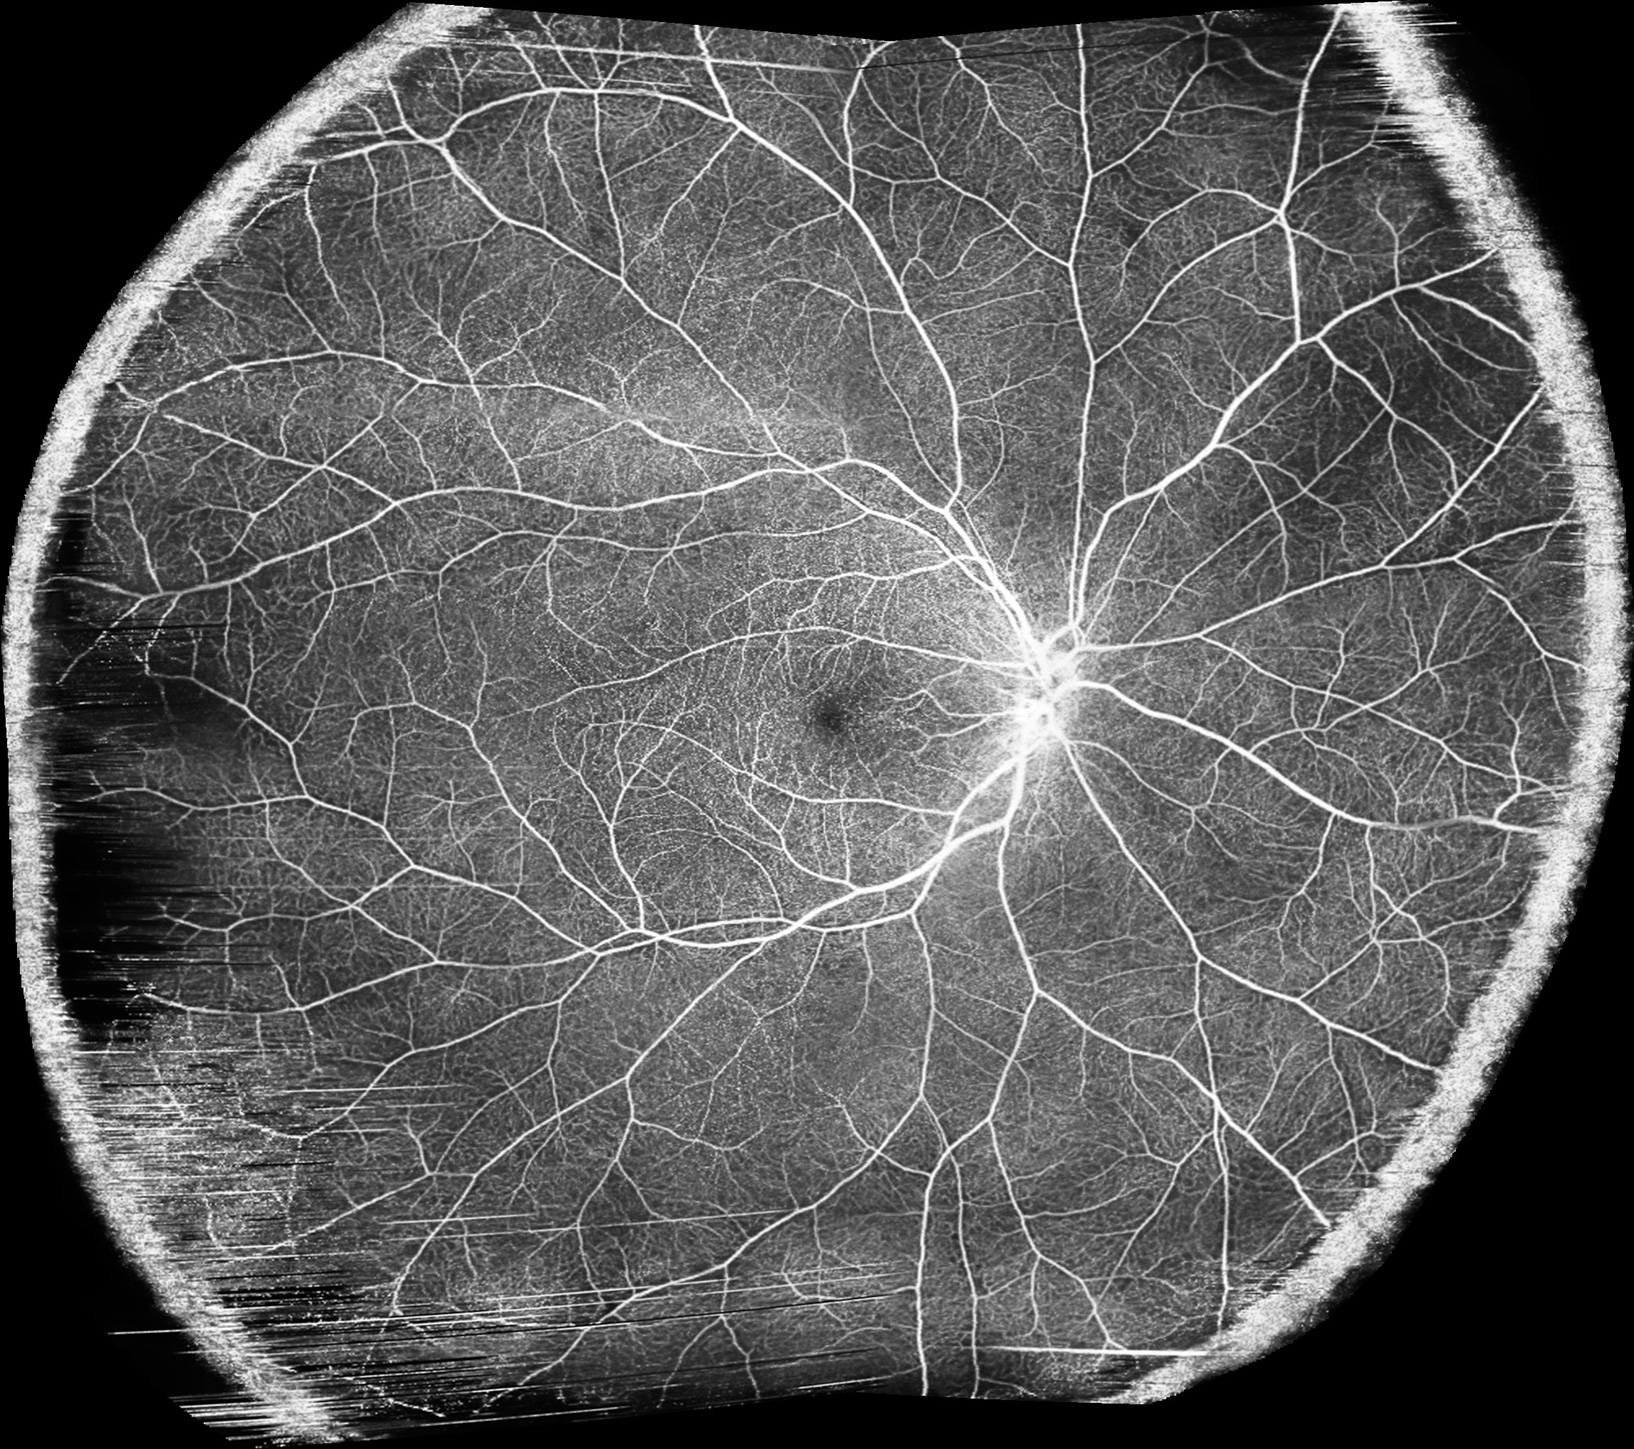

Революційна технологія частотно-модульованого джерела світла ОКТ Canon Xephilio OCT-S1 дозволяє отримати неперевершені за якістю томографічні зображення широкого поля зору до 23 мм за одне сканування.

OCT-S1 дозволяє отримати ультрашироке ОКТА зображення ділянки розміром 23 x 20 мм, що може бути дуже корисним для спостереження за товщиною сітківкі при відшаруванні сітківки або при пігментному ретиніті. Мозаїчне зображення ОКТА складається з 4 або 5 сканів ОКТА й загальне зображення має розмір 31 x 27 мм.

Серед оптичних когерентних томографів з частотно-модульованим джерелом лише Canon Xephilio OCT-S1 забезпечує ширину В-скана у 23 мм з глибиною 5,3 мм. Ви отримуєте більше діагностичної інформації за один скан з неперевершеною якістю зображення навіть при скануванні важких пацієнтів.

Малюнок 1. Очні патології на одному зображенні. Зображення надане доктором медицини Барбарою Пароліні, керівником вітреоретинального відділення Очної клініки, Брешія, Італія.

Малюнок 2. Скан 23 мм Canon OCT-S1 у порівнянні зі стандартним ОКТ сканом. Широкопольний ОКТ візуалізує набагато більшу ділянку сітківки, що не дозволить пропустити патологію периферії.

Малюнок 5. Мозаїчне широкопольне ОКТА зображення. Додаткова функція автомонтажу 4 або 5 зображень створює мозаїчне зображення з шириною скана ≈ 31 мм та висотою скана ≈ 27 мм. Діагональ комбінованого зображення може мати довжину приблизно 36 мм, що відповідає куту перегляду в 120°.